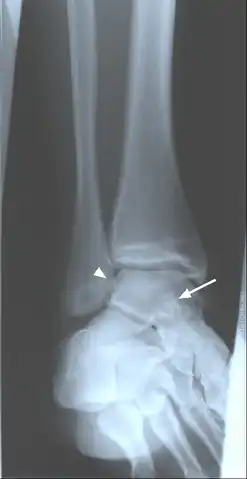

-

Oblique ankle radiograph with evidence of calcified loose bodies medial arrow head to the lateral maleolus and superimposed over the talus arrow, this suggests synovial chondromatosis -